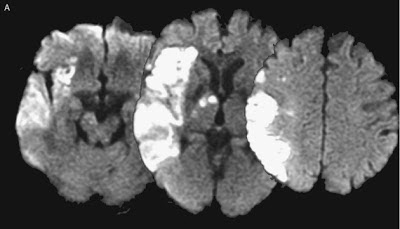

Does the right hemisphere play a unique role in maintaining a sense of self? A new case study by Nishio and Mori (2012) described a 69 year old patient who suffered a stroke affecting portions of the right frontal, temporal, and parietal lobes and right thalamus. A neurological exam a week later revealed severe hemispatial neglect of the left side of space, left sided weakness, motor neglect of his left limbs, and impaired senses of pain, cold, touch, vibration, and position on the left side of his body. These symptoms are typical of such a large right hemisphere lesion (see below).1

FIGURE 1. (Nishio & Mori, 2012). Magnetic resonance images of the patient’s brain, taken just after the onset of the stroke. The right side of the brain appears on the left side of the scans. A, Transverse diffusion-weighted images show fresh infarcts involving the right-frontal, temporal, and parietal lobes and thalamus.

What was unusual were other aspects of his behavioral presentation: